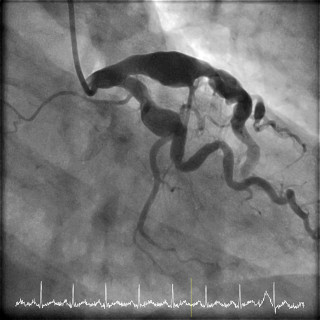

Hjertesykdommer